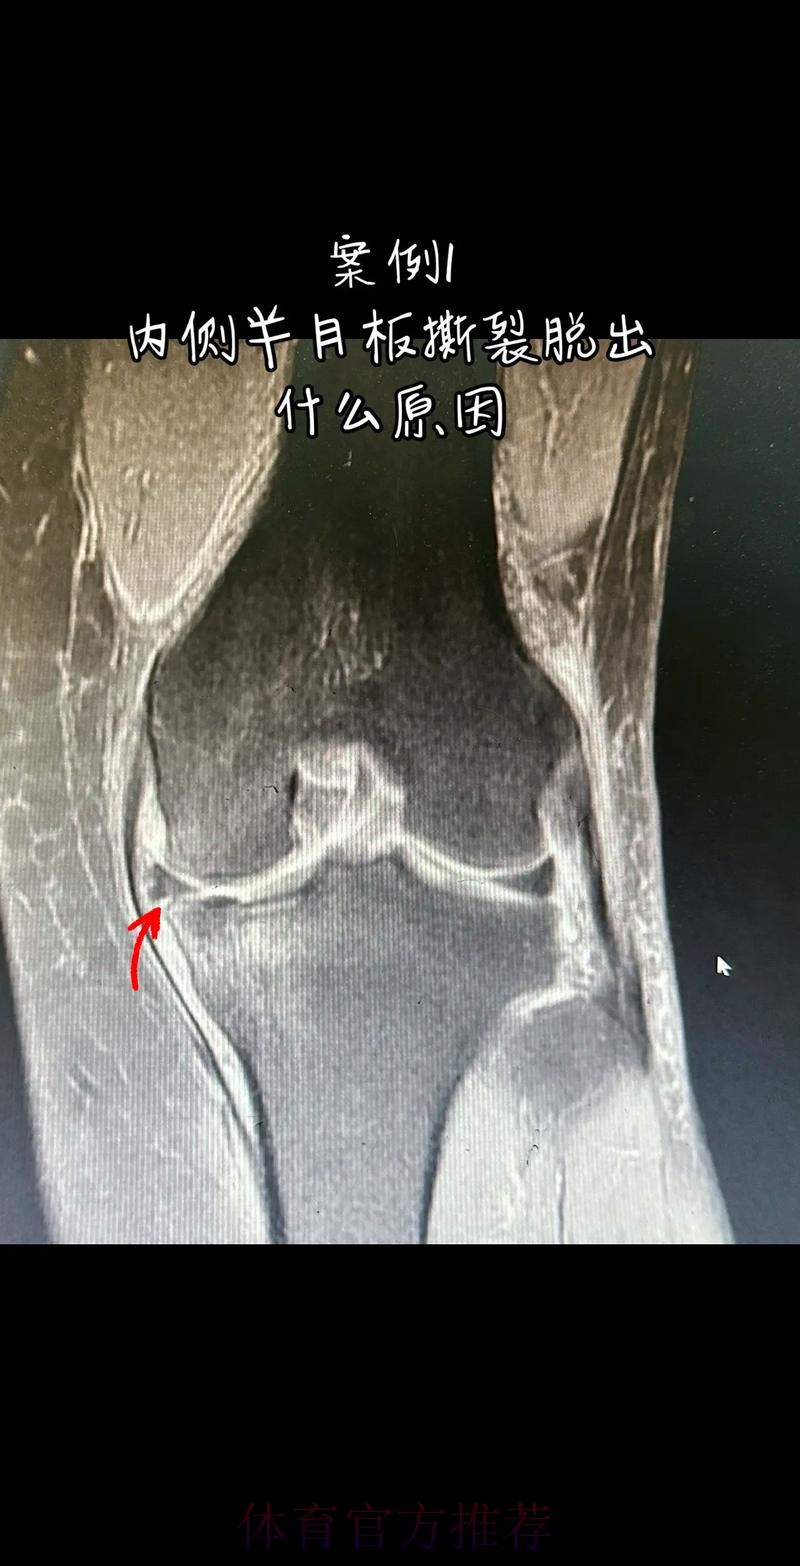

从医学角度看 半月板是膝关节内一块呈“C”形的软骨结构 其作用是缓冲冲击 稳定膝关节 并帮助分散压力 “左膝内侧半月板撕裂”通常说明在一次急停 旋转 或对抗中 半月板受到了超过其承受极限的力导致结构损伤 这类伤病常见于足球 篮球等需要频繁变向和对抗的项目 对于职业球员而言 半月板损伤严重程度不一 但共同点是都会影响支撑发力 跳跃以及变向时的稳定性 而官方给出的“预计伤缺6-8周”这个时间区间 往往对应的是中度损伤或通过微创手术加积极康复能够较快回归的情况 也意味着暂时没有出现必须长时间休战的最坏结果 表面上看 6-8周只是一个时间区间 但对顶级球队的赛程来说 这段时间可能包含多场联赛 甚至关键杯赛淘汰轮 相当于缺席一个赛季中最密集的一段周期 需要强调的是 这个“预计”并不是绝对数字 它取决于撕裂的位置 大小 修复方式 以及球员个体的恢复能力 有时若采取保守治疗 球员在6周时即可参与部分训练 但要达到比赛要求则可能接近8周甚至稍长 此外 精英运动员的康复不仅仅是伤口愈合 还包括力量恢复 协调重建 和心理自信的回归 阿拉巴要在有限时间内完成从“伤病患者”到“可靠首发”的角色转换 这一过程复杂程度远远超出一纸通告所能呈现